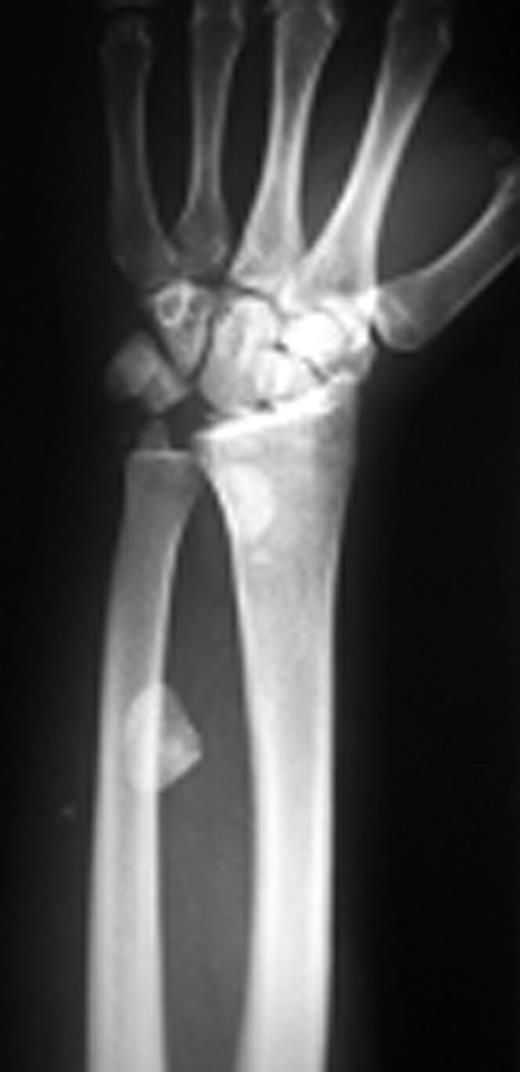

A 19-year old right hand dominant worker man presented after falling from height of about 6 meters onto his left hyperextened wrist. He was a multiple-injured case with closed fractures of femoral shaft and proximal phalanx of left second finger. In exam, wrist swelling was generally moderate with subtle deformity and ecchymosis in volar part. Range of wrist motion was very tender. A thorough serial neurovascular examination showed progressive paresthesia in median nerve territory checked by two points discrimination. Taken X-ray disclosed trans-scaphoid dorsal perilunate fracture dislocation and avulsion fracture of ulnar styloid. Excessive displacement of the lunate to middle third of the forearm and proximal scaphoid with multiple bony fragments to distal third was obvious (Figure 1a & 1b).

Posteroanterior and lateral X-rays of left wrist show perilunate fracture dislocation with excessive proximal displacement of lunate and proximal scaphoid. Loss of carpal height with broken Gilula’s arcs is obvious.